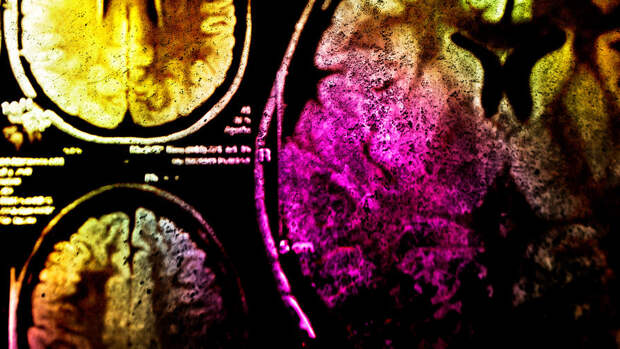

Марреро и его коллеги рассматривали истории болезни пациентов, изучали состояние мозга больных с помощью МРТ, делали токсикологические пробы, наблюдали за метаболизмом, брали анализ спинномозговой жидкости, исключали возможные диагнозы один за другим - слабоумие, нейродегенеративные и аутоиммунные заболевания, инфекционные болезни - ничто из этого не подходило.